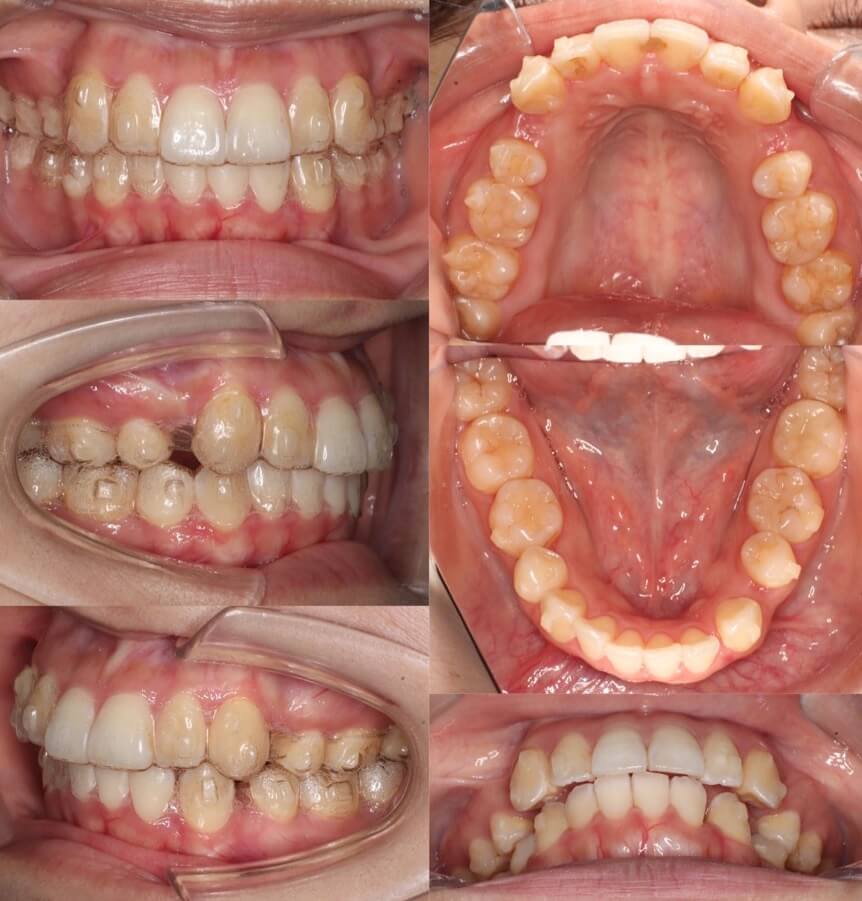

「男性は顔が引き締まる」

高校生男性・唇側矯正装置・下あご後退型

当初は、抜歯矯正治療にするかしないかで、治療方針に迷ったケースですが、最終的には患者さんの希望に沿って抜歯矯正治療にしました。歯の動きがゆっくりであったため、治療期間が3年を超えてしまいました。

<症例概要> 難易度:★★★★☆

主訴:口元の突出・前歯のガタツキ

年齢・性別:高校生男性

住まい:千葉県八千代市市

症状:下顎後退・叢生

治療方針:抜歯空隙の閉鎖(最大固定)

治療装置:唇側矯正装置

固定:歯科矯正用アンカースクリュー(頬側x2)

抜歯:上下第一小臼歯(計4本)

治療期間:3年4か月

リテーナー:上下プレートタイプ+フィックスタイプ

治療費用:968,000(税込)

代表的副作用:痛み・治療後の後戻り・歯根吸収・歯髄壊死・歯肉退縮